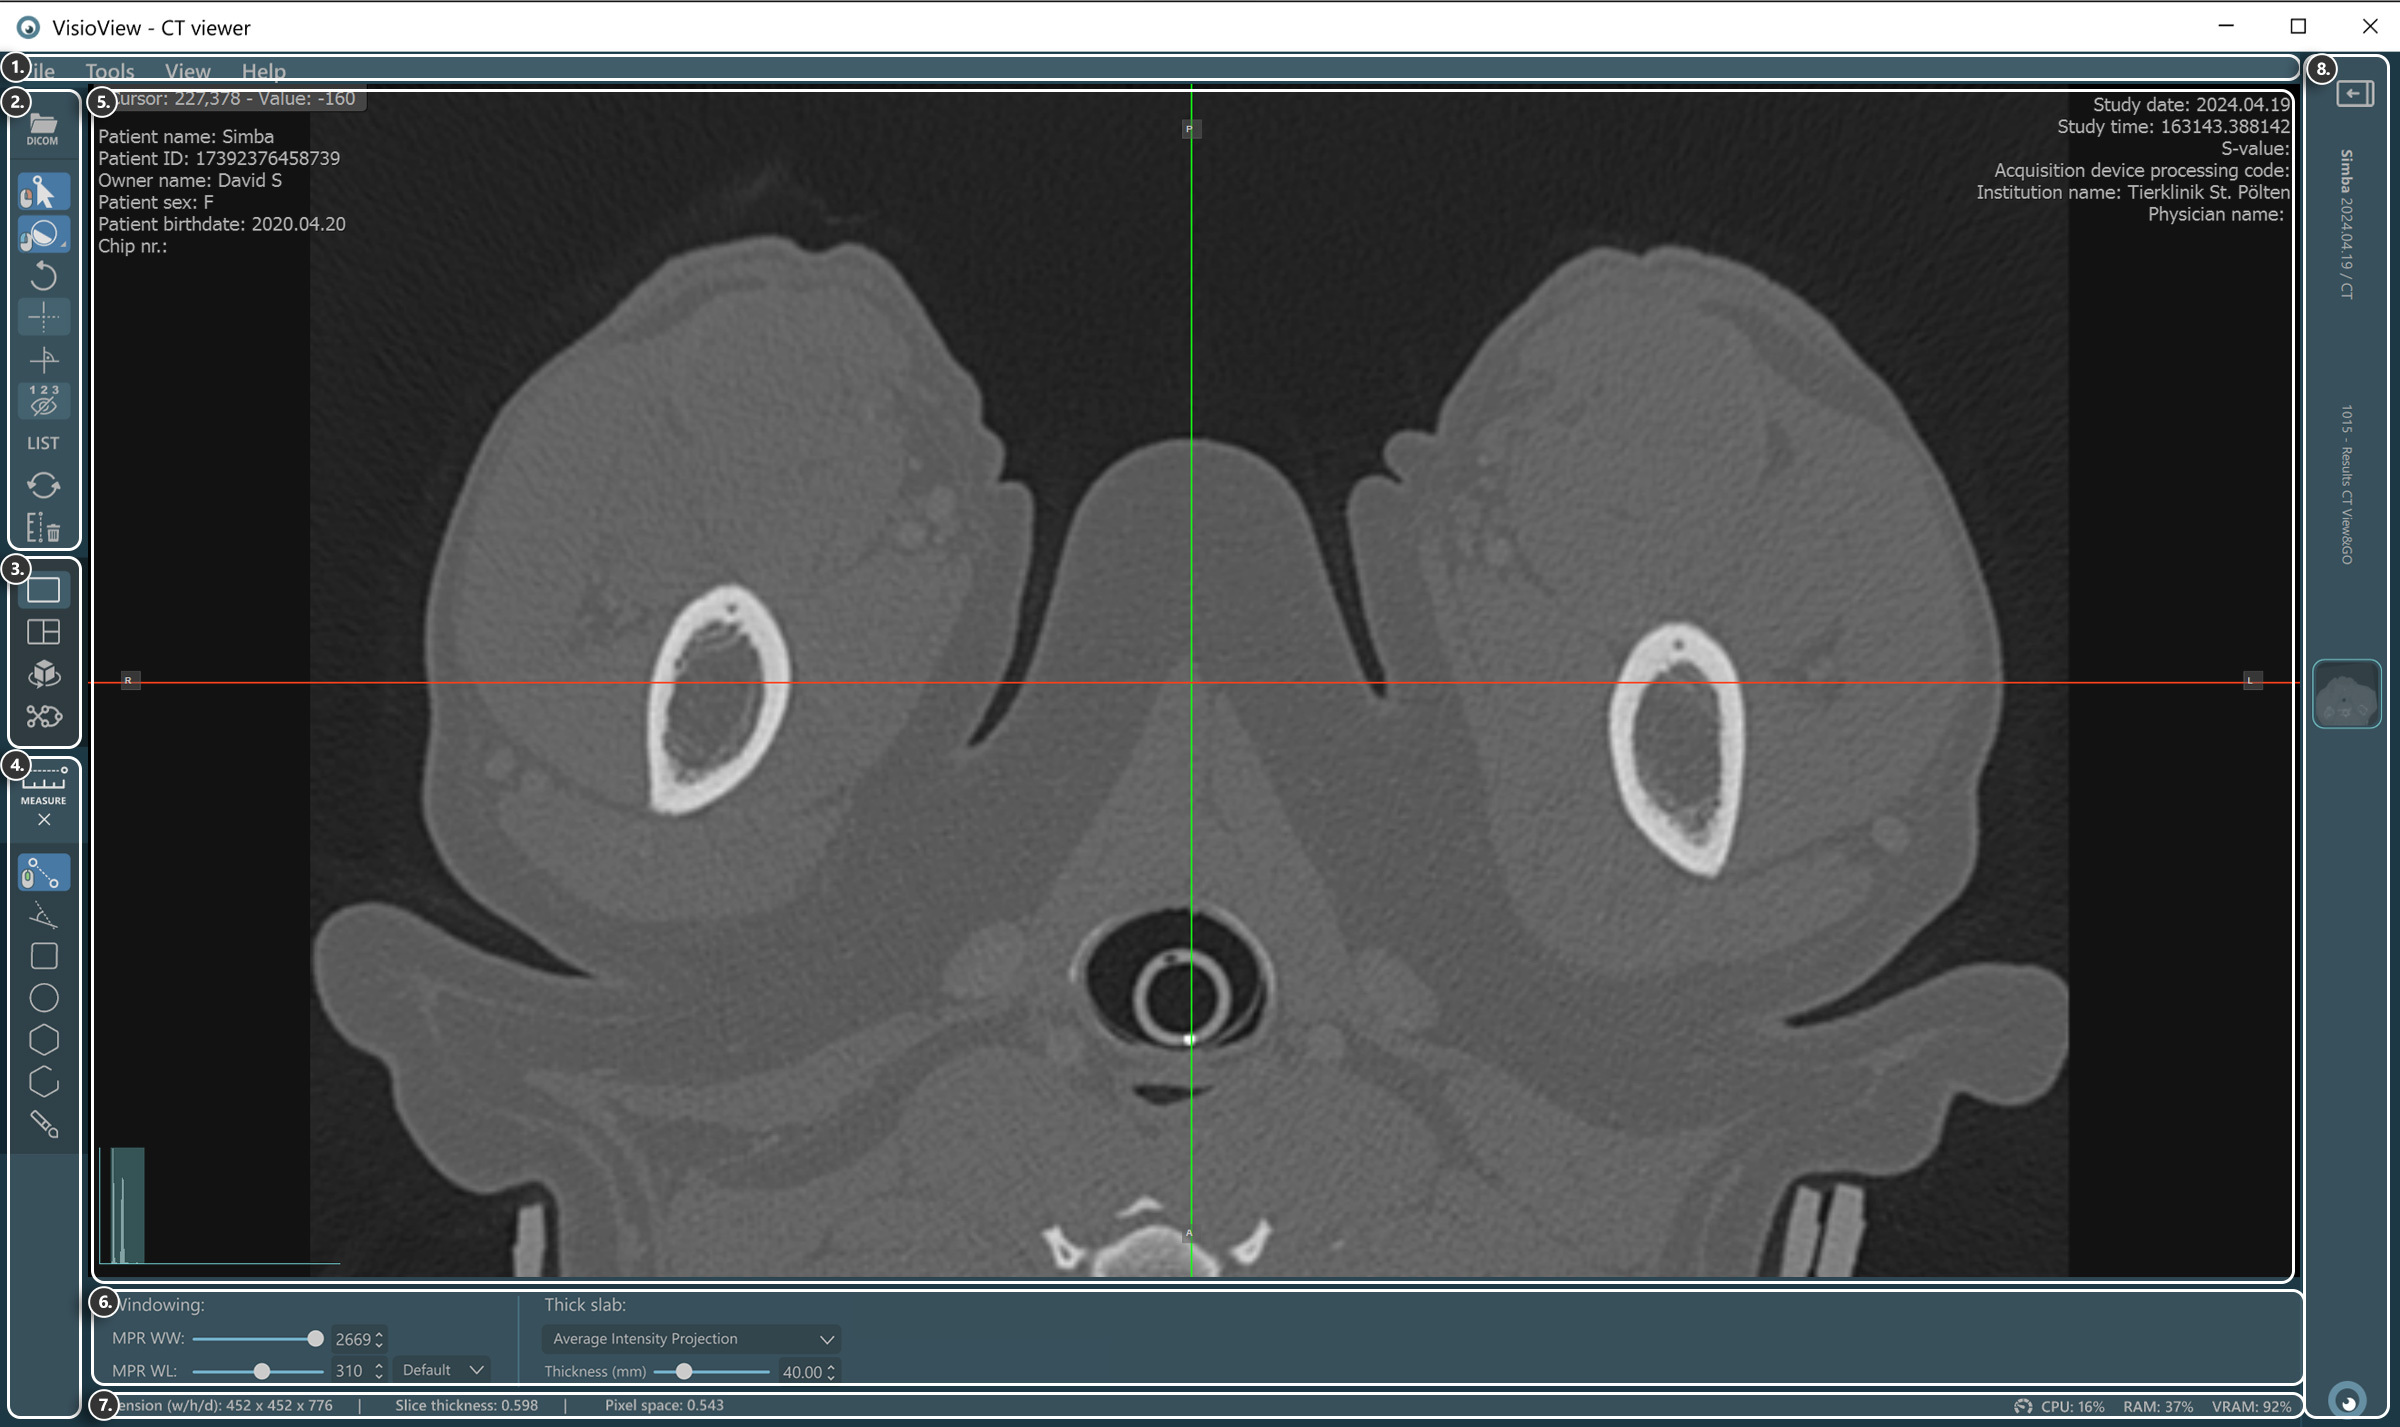

VisioVIEW – CT-Viewer¶

Der neue VisioVIEW CT-Viewer ist ein dedizierter DICOM-Viewer, der in der Lage ist, 3D-Multiplan-Rekonstruktionen (MPR) von volumetrischen DICOM-Bildern (CT- und MR-Modalitäten) durchzuführen. Zusätzlich unterstützt er weitere Ansichtsmodi, darunter eine 3D-Ansicht, die eine gleichzeitige Untersuchung aller 3D-Ebenen (Axial, Koronal und Sagittal) und die 3D-Visualisierung des Körpers ermöglicht, eine Curved-MPR-Ansicht (CMPR), Average-Intensity-Projektion, Maximum-Intensity-Projektion (MIP) und Minimum-Intensity-Projektion (MinIP).

Abschnitte des VisioVIEW CT-Viewers¶

Der VisioVIEW CT-Viewer besteht aus mehreren Abschnitten, die jeweils einem bestimmten Zweck dienen. Im Folgenden finden Sie eine detaillierte Beschreibung jedes Abschnitts.

Werkzeuge und Optionen¶

Ansichts-Selektor¶

Messwerkzeuge¶

Viewer-Bereich¶

Anzeigeeinstellungen und Optionen¶

Windowing-Einstellungen

Einstellungen für dicke Schichten

Informationsleiste¶

DICOM-Bild- und Auflösungsinformationen

Leistungs und Ressourcennutzungsinformationen